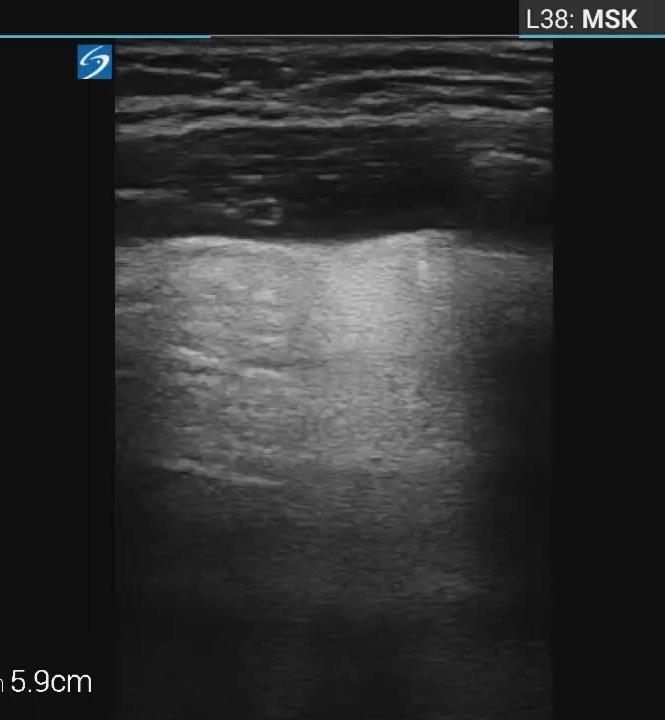

Pediatric COVID-19: MIS-C

Thoracic abnormalities

Abdominal abnormalities

Solid viscera abnormalities

Hepatomegaly

Echogenic kidneys

Splenomegaly

Hollow viscera abnormalities

Gallbladder wall thickening

Bowel wall thickening

Bowel dilation

Gastric distention

Urinary bladder thickening

Peritoneal abnormalities

Small ascites

Mesenteric abnormalities

Mesenteric lymphadenopathy